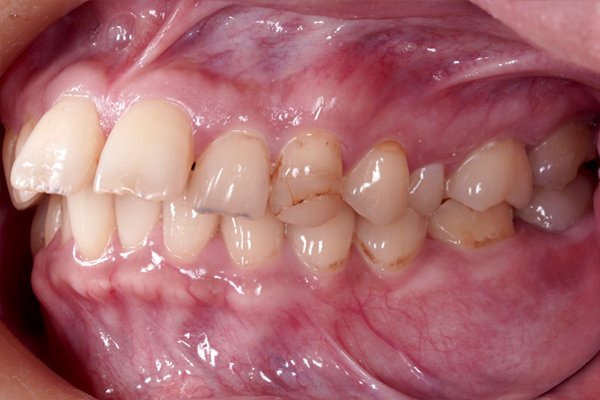

横からの比較(右側)

横からの比較(左側)